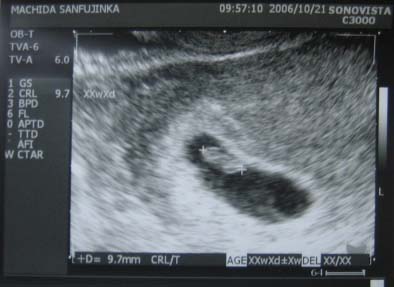

妊娠検査薬はほぼ間違いないし、改めて「妊婦認定」(?)してもらいに行ったような気持ちでしたが、

エコーで、「このチカチカしてるのが心拍ね。」と、見せてもらったときは、さすがに

カンド-----!!!

しました

しかしまだ少し早かったようで、予定日とか母子手帳の話は、次回(2週間後)となりました。

そのときの写真がコレ↓

予想はしていたけど、やっぱり何がなんだか・・・

でも「順調ですね」という先生のお言葉に、なんだか安心しました♪